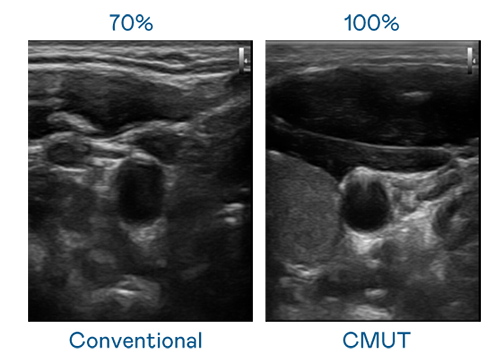

CMUT 技术是一种用电容式微机电元件来产生超音波讯号的技术。与传统 PZT 压电式技术相比,CMUT 频宽增加 30%,更宽频的超音波讯号让影像解析度大幅提升,是实现高影像品质医疗超音波扫描、促进精准医疗发展的关键技术。

大频宽带来超清晰影像

超音波影像的解析度高低,首先取决于探头能发出的讯号频宽。k8凯发(中国) CMUT 可提供高清晰的超音波讯号,提供高频宽、高灵敏度、影像纹理细节更高的超音波影像,协助医护人员缩短影像判读时间及利用精准的医疗影像进行诊断。